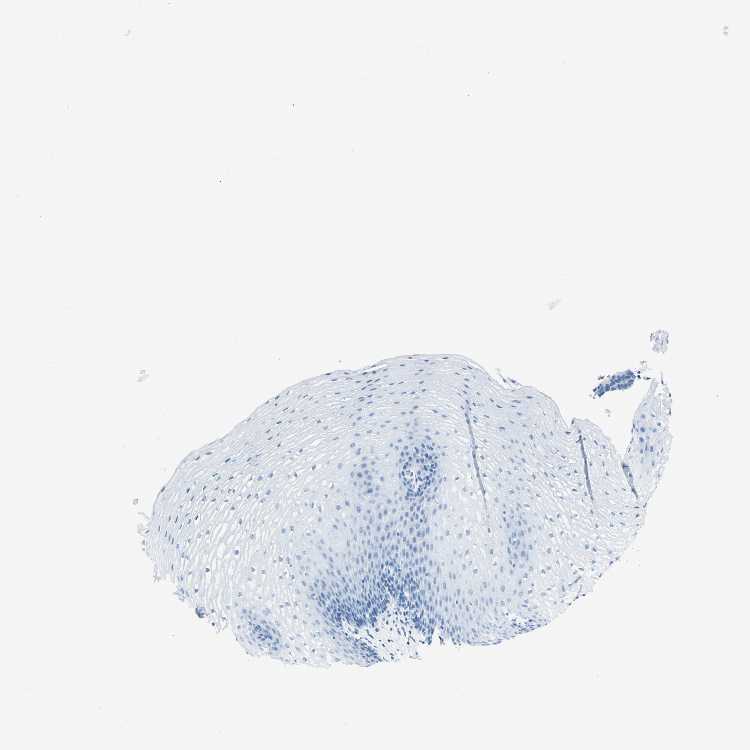

ESOPHAGUS - Antibody stainingi

Antibody staining in the annotated cell types in the current human tissue is reported as not detected, low, medium, or high, based on conventional immunohistochemistry profiling in selected tissues. This score is based on the combination of the staining intensity and fraction of stained cells.

Each image is clickable and will lead to virtual microscopy that enables deeper exploration of all samples and also displays staining intensity scores, fraction scores and subcellular localization as well as patient and tissue information for each sample.

Antibody HPA010593Antibody CAB001451

Squamous epithelial cells Not detectedNot detected